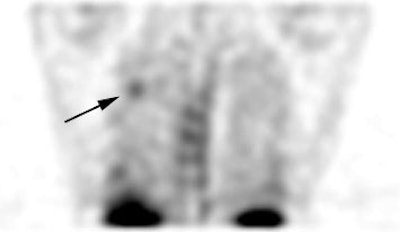

True positive Neotect exam: CT scan demonstrated an irregular nodule within the right upper lobe. Coronal Neotect image demonstrated abnormal tracer accumulation in the lesion. The lesion was surgically resected and found to be NSCLC. Case courtesy Dr. Jamie Montilla. |